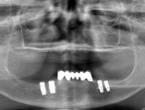

レントゲン

下顎のインプラント治療

CT撮影したデータをコンピュータ上で立体的にシミュレーションして最適なインプラント治療計画を行いました。その結果、下顎は歯肉を切ることなく無切開(フラップレス)での手術が可能になりました。そして、確実な初期固定が得られたため手術後すぐに義歯の固定を行いました。また、歯科麻酔専門医による静脈内鎮静麻酔を行ったため、患者さんは痛みや不快感を感じることなく手術を終えることができました。